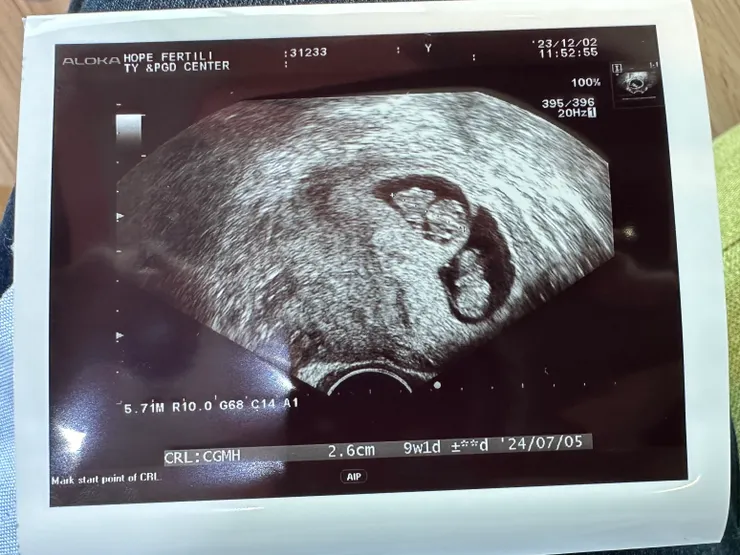

剛好滿9w的小朋友們

- A寶-9w1d、2.6cm

- B寶-9w1d、2.6cm

這次沒有聽心跳,不過兩個小朋友都追上了彼此的成長進度,看樣子媽媽每天喝滴雞精是真的有效唷👍🏻